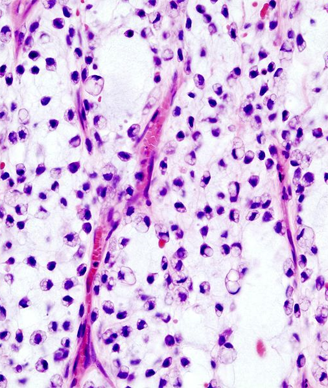

Surgery is the mainstay of treatment for localized soft-tissue sarcoma (STS). It consists primarily of resection of the tumor along with a cuff of surrounding healthy tissue. In limb and trunk wall sarcomas, this basically implies resection of the surrounding soft tissues, which are mainly muscles, subcutaneous fat, and skin.[1] In the retroperitoneum, this necessarily should imply resection of adjacent viscera, even when they are not overtly involved.[2] This is the only way to avoid/minimize the presence of tumor cells at the cut surface (ie, positive microscopic surgical margins). Positive microscopic surgical margins are associated with a higher risk of local failure, distant metastases, and death.[3-6] Moreover, for STS located at critical sites, such as retroperitoneal sarcoma (RPS), positive surgical margins may have a direct impact on survival, favoring the development of inoperable local recurrences.[7] Indeed, unlike with STS arising in the extremities and trunk wall, local control in RPS poses a significant challenge and remains the leading cause of death, particularly in patients with low- to intermediate-grade tumors-roughly 75% of all cases.[8-13] Extending the resection to adjacent uninvolved viscera for primary RPS is the only way to minimize the presence of microscopic surgical margins and hence maximize the chance of cure. In essence, this strategy should often include ipsilateral nephrectomy and colectomy; locoregional peritonectomy and myomectomy (partial/total) of the muscle of the lateral/posterior abdominal wall (usually the psoas) (see Figure); splenectomy and left pancreatectomy, for tumors located on the left upper side; occasionally pancreaticoduodenectomy or hepatectomy, for tumors located on the right side; and vascular and bone resection only if vessels/bone are overtly infiltrated.[2]